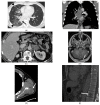

KRAS G12C mutations are important oncogenic mutations that confer sensitivity to direct G12C inhibitors. We retrospectively identified patients with KRAS+ NSCLC from 2015 to 2019 and assessed the imaging features of the primary tumor and the distribution of metastases of G12C NSCLC compared to those of non-G12C KRAS NSCLC and NSCLC driven by oncogenic fusion events (RET, ALK, ROS1) and EGFR mutations at the time of initial diagnosis. Two hundred fifteen patients with KRAS+ NSCLC (G12C: 83; non-G12C: 132) were included. On single variate analysis, the G12C group was more likely than the non-G12C KRAS group to have cavitation (13% vs. 5%, p = 0.04) and lung metastasis (38% vs. 21%; p = 0.043). Compared to the fusion rearrangement group, the G12C group had a lower frequency of pleural metastasis (21% vs. 41%, p = 0.01) and lymphangitic carcinomatosis (4% vs. 39%, p = 0.0001) and a higher frequency of brain metastasis (42% vs. 22%, p = 0.005). Compared to the EGFR+ group, the G12C group had a lower frequency of lung metastasis (38% vs. 67%, p = 0.0008) and a higher frequency of distant nodal metastasis (10% vs. 2%, p = 0.02). KRAS G12C NSCLC may have distinct primary tumor imaging features and patterns of metastasis when compared to those of NSCLC driven by other genetic alterations.